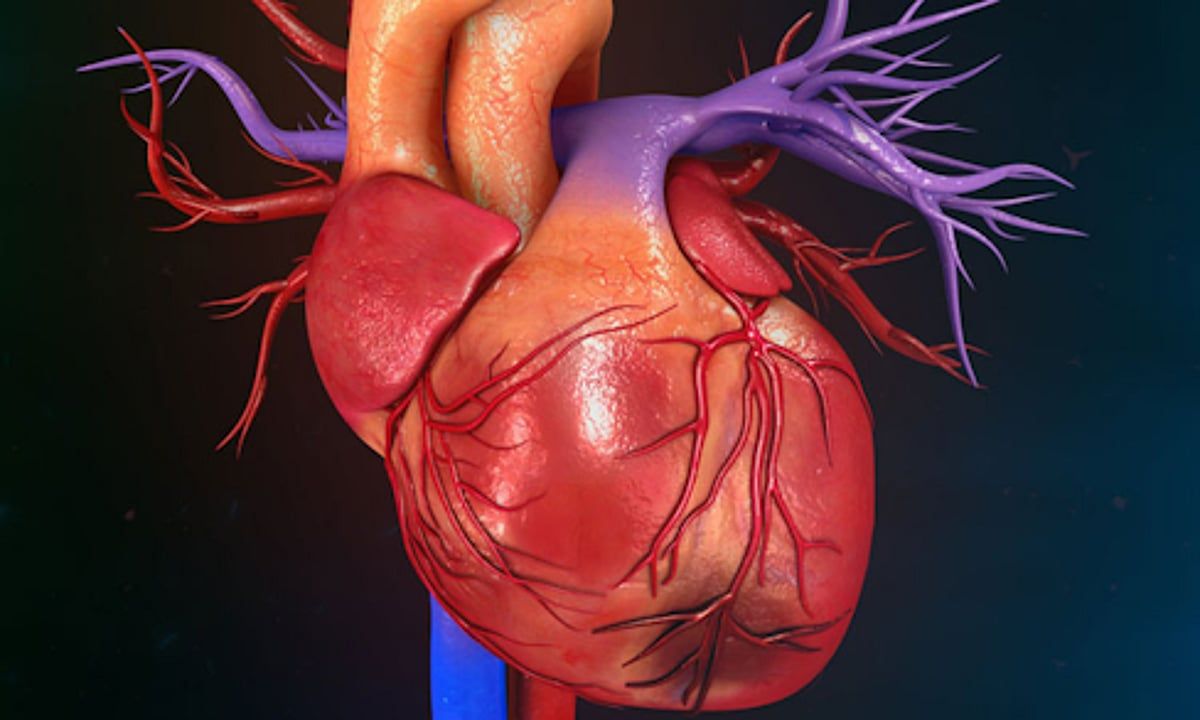

وافقت هيئة الغذاء والدواء الأمريكية "FDA" على بدء التجارب السريرية على دواء جديد لتجديد أنسجة القلب، وهو إنجاز طبي جديد يمثل أملاً جديدًا للمرضى الذين يعانون من أمراض القلب.

ووفقًا لتقرير على موقع "News medical life science"، يقوم باحثون من جامعة كاليفورنيا الأمريكية بتطوير هذا الدواء، الذي يعمل على تثبيط إنتاج بروتين ENPP1، الذي يعطل توليد الطاقة ووظيفة خلايا القلب.

أوضح الباحثون أن عينات أنسجة القلب المأخوذة من الفئران والبشر بعد نوبة قلبية أظهرت ارتفاعًا في مستويات بروتين ENPP1، وأن تثبيط إنتاج هذا البروتين عزز إصلاح القلب وقلل من تكوّن النسيج الندبي.

وقال أرجون ديب، عالم أمراض القلب والأوعية الدموية في جامعة كاليفورنيا، لوس أنجلوس: "إذا أظهرت التجارب السريرية أن الدواء فعالٌ لدى البشر كما هو الحال لدى الحيوانات، فقد يكون AD-NP1 الأول ضمن فئة جديدة كليًا من الأدوية المُعزِّزة لإصلاح الأنسجة التي تمنع تدهور وظائف الأعضاء".

يعتمد الدواء على جسم مضاد وحيد النسيلة يُسمى AD-NP1، يعطل وظيفة ENPP1 ويُعزّز إصلاح أنسجة القلب وأعضاء أخرى. وقد أظهرت التجارب على الحيوانات أن عضلة القلب تحتوي على المزيد من الطاقة وانقبضت بشكل أكثر قوة، مما منع تطور قصور القلب. يأمل ديب أن يبدأ فريقه التجارب على البشر قريبًا.